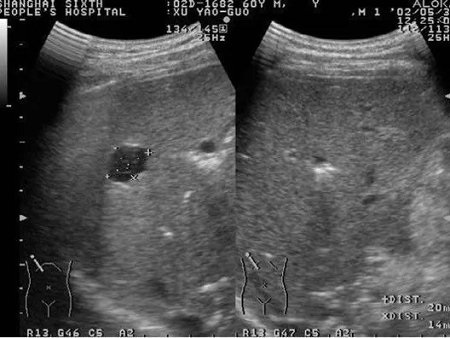

医生通过检查可诊断。但是如果小红点不沿皮肤表面弥散生长,而是向皮肤深部生长,皮肤表面可能看不出明显变化,但是却能发现高出皮肤的肿块或两侧皮肤不对称。这时可能会给医生的诊断带来困扰,这就需要借助彩超,在我们眼睛看不见的皮肤深面,了解肿块的性质,帮助医生更清楚的诊断(图4)。

▲ 图4